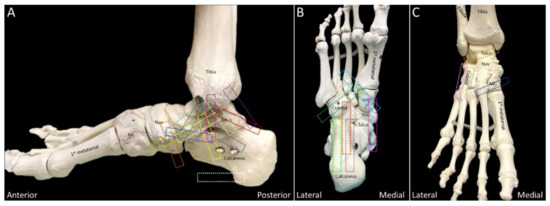

2.10. Lisfranc Ligament Complex

2.10.1. Anatomy

2.10.2. Scanning Technique

2.10.3. Clinical Relevance

2.11. Lateral Cord of the Plantar Fascia

2.11.1. Anatomy

2.11.2. Scanning Technique

2.11.3. Clinical Relevance